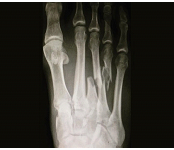

Diploma Orthopedics, Fellowship in Foot & Ankle Surgery from Vadodara, Chennai, Spain, U.K.

1st and only exclusive foot & Ankle surgeon of Saurashtra-Kutch region. Practicing orthopedics since 2014 with dedicated practice of ankle and foot surgeon since 2021